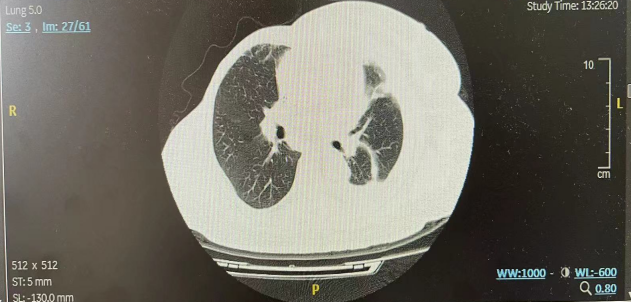

二线治疗前(2022年7月)患者再次出现高热,于外院诊断肺炎(图2)。抗炎治疗3周后,肺炎有所好转(图3),体温恢复。

图2.二线治疗前胸部CT示左肺炎

图3.抗炎治疗3周后胸部CT示左肺炎好转

二线治疗思考: